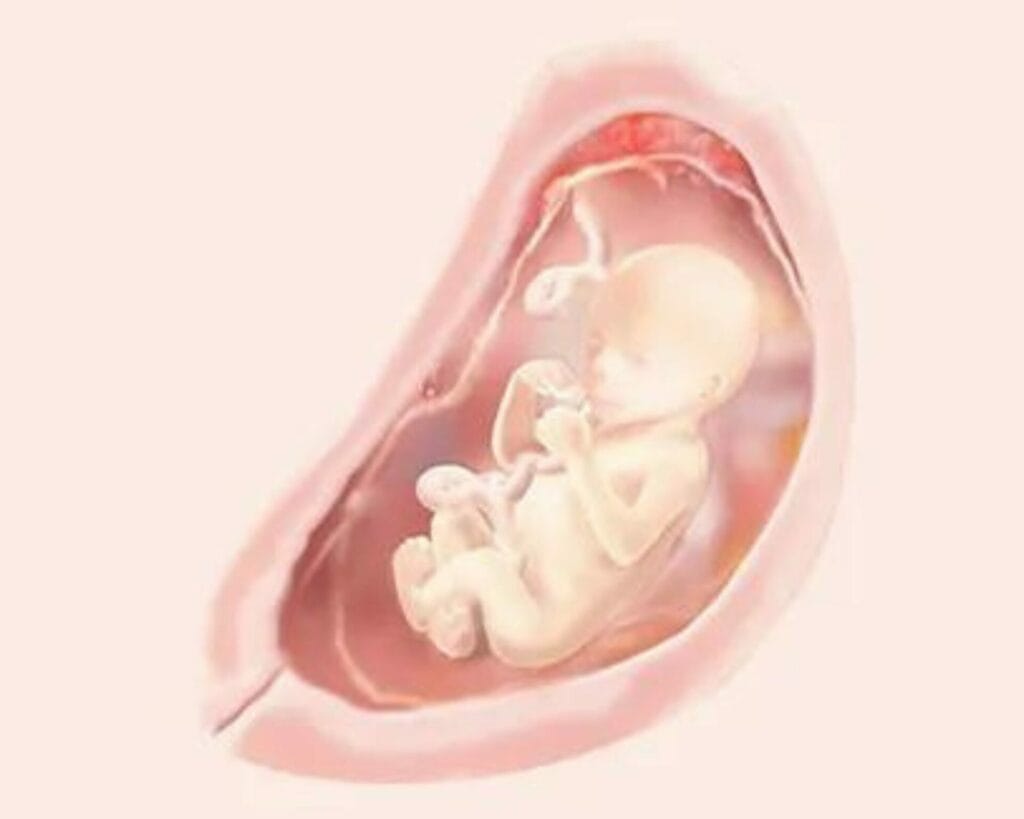

في الأسبوع التاسع عشر من الحمل فمن المحتمل أنك قد تبدأي في شعور بحركات صغيرة من طفلك مع إستمراره في النمو، وستصبح هذه الحركات الصغيرة التي تشبه الفقاعات، حيث تتحول إلى ركلات وتثقيب وتقلبات ومنعطفات.

أصبحت ذراعي طفلك وساقيه متناسقتين وتتحركان بمزيد من التحكم في الأطراف حيث يبدأ الغضروف في التصلب حتى العظم.

تفقد البشرة الآن مظهرها الشفاف وتبدأ في تطوير صبغة تحديد لون البشرة سيتم تغطيتها أيضًا بمادة Vernix CCaseos، وهي مادة رقيقة مثل الشمع تساعد على حماية جلد طفلك من السائل الأمنيوسي إنه موجود لحماية بشرة طفلك الرقيقة والحساسة من آثار الجفاف والسقوط الناتجة عن السائل الأمنيوسي، وتنظيم درجة حرارة الجسم للطفل يولد البعض مع بقايا vernix في الواقع إنه أحد الأسباب التي تجعل الأطفال يتمتعون بشرة ناعمة بعد الولادة أيضاً يعمل Vernix على مساعدة طفلك على المرور عبر قناة الولادة بسهولة أكبر.

يبدأ نمو شعره على فروة رأسه على الرغم من أنه سيكون أبيضًا وخالٍ من الصبغات، حيث أنه لم يتم تحديد لون الشعر بعد، وتبدأ الأسنان الخلفية الدائمة لطفلك بالنمو بالفعل، ولكن على شكل براعم.

إذا سمعتي نبضات قلب طفلك ستشعرين أنه أسرع من نبضات قلبك، ويستمر دماغ الطفل في النمو وأيضا حواسه الخمس الشم والتذوق والسمع والرؤية واللمس من الممكن أن يتمكن من سماع صوتك الآن.

يبدأ الجسم في تخزين الدهون في الأشهر الثلاثة الأولى وهذا يتوقف في منتصف الحمل في هذا الأسبوع يبدأ الجنين في استخدام الدهون المخزنة، والتي توفر الدفء بعد الولادة.

إذا كان لديكي فتاة في هذا الاسبوع فهناك بالفعل حوالي ستة ملايين بويضة في مبيضها، ولكن إذا كان لديكي ولد فإنه لا ينمو لديه الآن حيوانات منوية فقط إلا عند البلوغ.